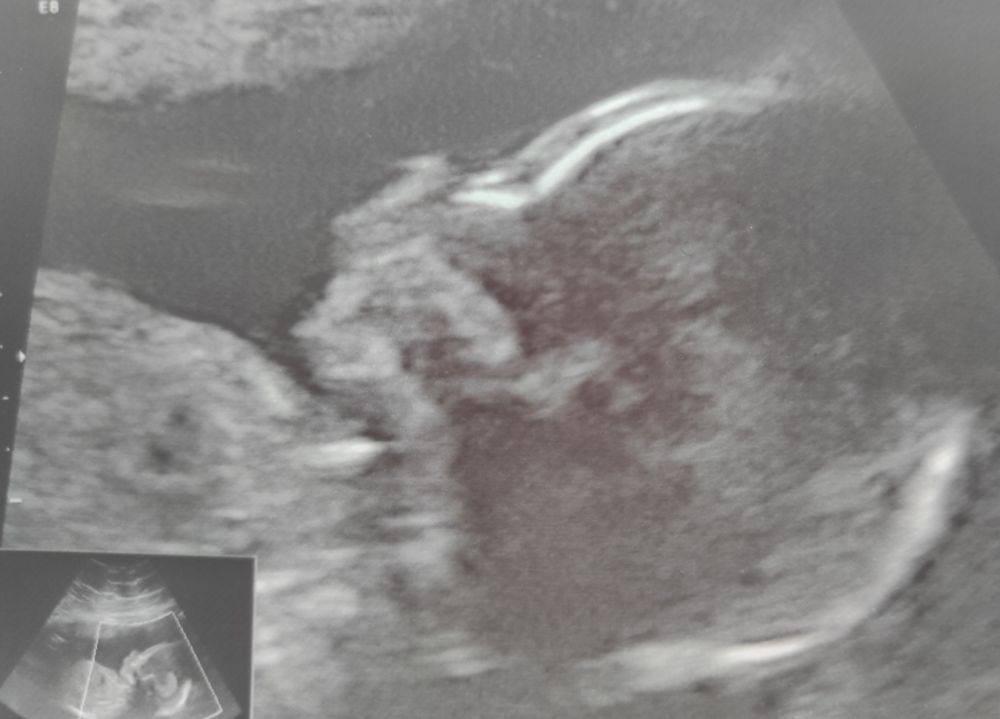

18 недель😇

Сходили сегодня с мужем на УЗИ ради моего спокойствия... Растёт пупс😍помахал нам ручкой✋померяли воды.. Шейку.. Послушали ❤второй скрининг через 2 недели.. Жду привета от малыша в виде пиночков... Скорее бы.. Расти наша прелесть🥰